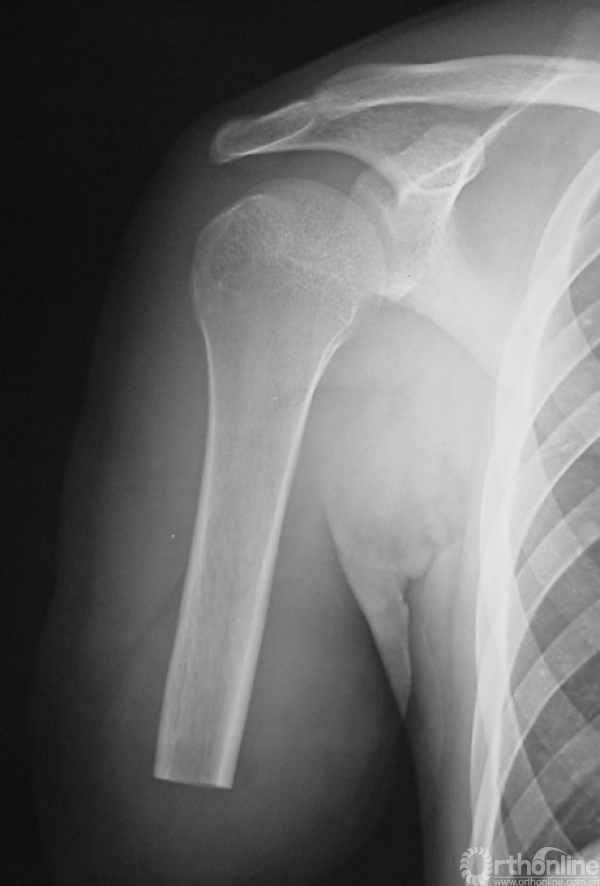

男性,16岁。患者入院3个月前摔伤右前臂,即出现疼痛、肿胀、活动受限。

图14-1 伤后X线平片正侧位

1.有外伤病史,但无骨折前局部疼痛等症状。而是在低暴力创伤的情况下出现骨折,可能并非单纯创伤暴力所致。

2.X线平片显示右桡骨干骨皮质不连续,骨折端内可见边界不清之溶骨破坏,其内密度不均,应该首先考虑为病理骨折,但又未见明确的骨膜反应和软组织包块。所以应继续进行检查,包括细致的影像学检查如局部加强CT来判断是否确为病理骨折、是否有皮质破坏及软组织包块。